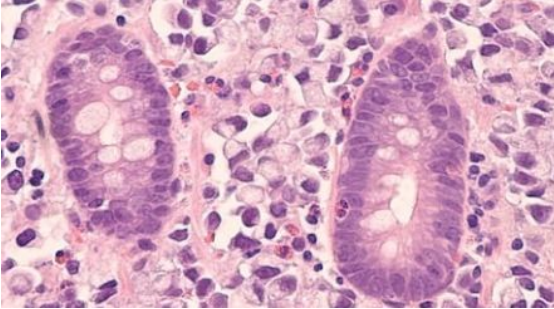

干細(xì)胞歸巢是指內(nèi)源或外源性干細(xì)胞在多種因素的作用下,能定向趨向性遷移,越過(guò)血管內(nèi)皮細(xì)胞至靶向組織并定植存活的過(guò)程,類(lèi)似人體局部炎癥反應(yīng)后大量白細(xì)胞遷移至炎癥周?chē)?/span>

血管中的 MSCs 黏附于毛細(xì)血管壁跨內(nèi)皮細(xì)胞層歸巢至目標(biāo)組織,MSCs和細(xì)胞外基質(zhì)通過(guò)表達(dá)細(xì)胞黏附分子配體與細(xì)胞黏附分子結(jié)合,介導(dǎo)干細(xì)胞歸巢到特定的靶點(diǎn)。